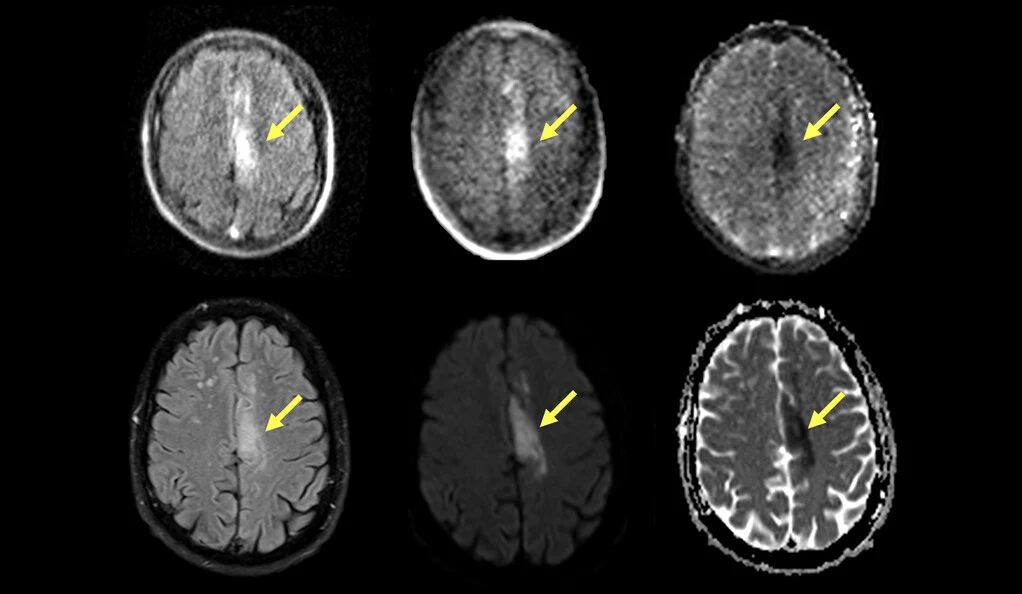

Przenośne aparaty MRI to zupełnie nowa technologia, która umożliwia obrazowanie medyczne nawet w odległych miejscach. Badania przeprowadzone przez naukowców z Uniwersytetu Yale i Harvarda wykazały, że tego typu aparaty pozwalają na wykrycie udaru niedokrwiennego lub udaru spowodowanego zakrzepem u 90 proc. skanowanych pacjentów.

Wcześniejsze badania wykazały, że przenośne urządzenia MRI mogą również wykrywać udary spowodowane krwawieniem w mózgu, które różnią się od udarów spowodowanych zakrzepami w mózgu. Zdolność przenośnych aparatów MRI do rozróżniania tych dwóch rodzajów udaru pomoże lekarzom szybko podejmować kluczowe decyzje dotyczące leczenia ratującego życie pacjentów w odległych rejonach, którzy nie mają dostępu do dużych szpitali wyposażonych w drogie stacjonarne aparaty MRI.

Naukowcy z Yale i Harvardu stwierdzili, że wyniki w dużej mierze potwierdzają diagnozy udaru niedokrwiennego postawione przez stacjonarne MRI. U 45 z tych pacjentów przenośny rezonans magnetyczny wykrył skrzepy krwi o wielkości zaledwie 4 mm. Prof. Sheth i jego zespół otrzymali fundusze od NIH na przeprowadzenie szeroko zakrojonych badań nad wykorzystaniem przenośnego rezonansu magnetycznego w różnych warunkach.